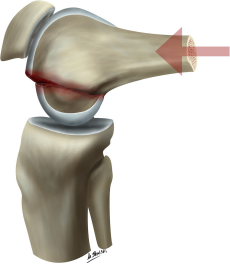

Hoffa骨折多为高能量损伤,青壮年多见。损伤机制多为膝关节屈曲时,轴向剪力作用于股骨髁后部所致。屈膝内翻或外翻情况下紧急制动,自股骨近端传导的轴向暴力作用于股骨髁,同时来自胫骨远端的暴力传导至胫骨平台,使股骨髁与胫骨平台之间产生巨大的剪切力,从而导致Hoffa骨折。常见于车祸伤、高处坠落伤。

当高能量暴力作用于股骨远端时,由于股骨远端存在外翻角的解剖特点,往往首先作用于外侧髁,因此,外髁Hoffa骨折明显多于内髁Hoffa骨折。